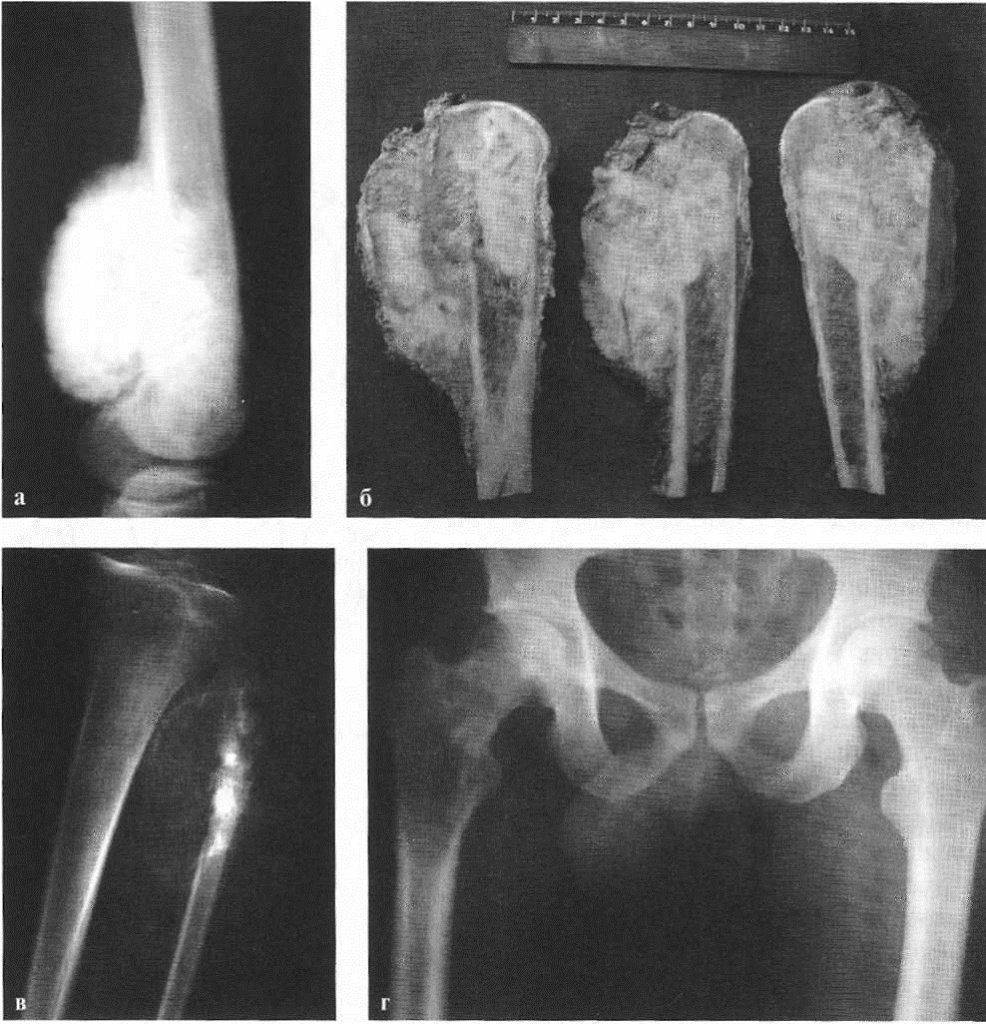

Рентгенологическая картина остеогенной саркомы кости - 98 фото